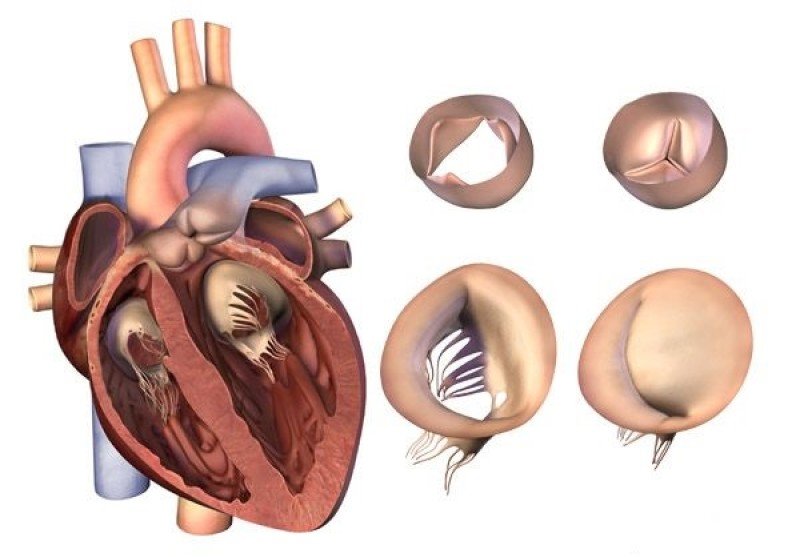

Фотографии и информация о приобретенных пороках сердца